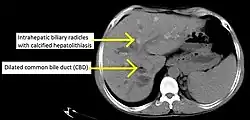

CT scan findings in a case of primary sclerosing cholangitis

PSC is generally diagnosed on the basis of having at least two of three clinical criteria after secondary causes of sclerosing cholangitis have been ruled out:

• serum alkaline phosphatase (ALP) > 1.5x the upper limit of normal for longer than 6 months

• cholangiography demonstrating biliary strictures or irregularity consistent with PSC

• liver biopsy consistent with PSC (if available)

Historically, a cholangiogram would be obtained via endoscopic retrograde cholangiopancreatography (ERCP), which typically reveals "beading" (alternating strictures and dilation) of the bile ducts inside and/or outside the liver. Currently, the preferred option for diagnostic cholangiography, given its noninvasive yet highly accurate nature, is magnetic resonance cholangiopancreatography (MRCP), a magnetic resonance imaging technique. MRCP has unique strengths, including high spatial resolution, and can even be used to visualize the biliary tract of small animal models of PSC.[22]